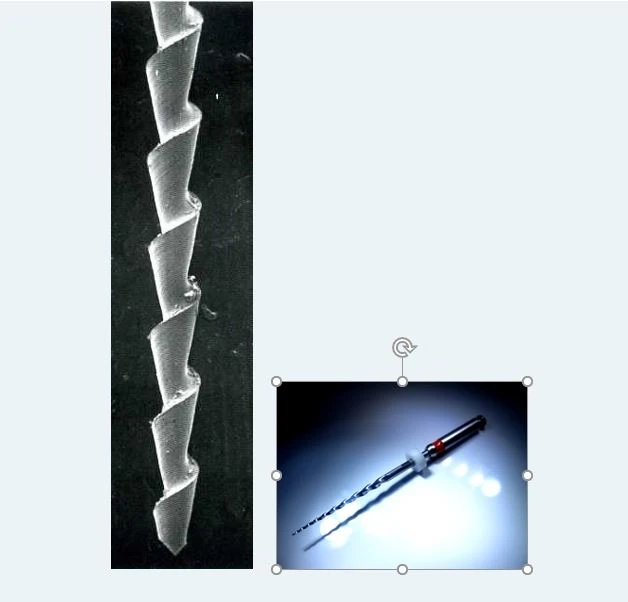

Kém hơn một chút là dùng cône GT trám và lèn chặt 1/3 chóp rồi bơm GP lỏng vào rồi nhồi xuống,rẻ nhất nhưng cũng khó sử dụng nhất là dùng gutta condensor GC ( dụng cụ quay này có cấu tạo gần như ngược với Hedstrom file ,khi cắm vào tay khoan khuỷu ,quay với vận tốc 30.000 vòng/phút thì nó sẽ làm GP bị nóng chảy và nén xuống ) nhưng sử dụng nó đòi hỏi phải có kinh nghiệm.

Tôi đã từng gặp một ca cây Gutta condensor khi ob răng 24 đã chạy tọt vào xoang hàm ! và do chạy với vận tốc cao trong một khối GP dù nóng chảy nhưng vẫn có lực cản rất lớn nên việc bị gãy GC xảy ra như cơm bữa và hầu như chỉ có những người giàu kinh nghiệm mới dám xài ! Muốn an toàn,phải bít rồi lèn 1/3 phía chóp Ống tủy hình chữ C thật chặt và khi đưa GC xuống thì chỉ đưa sâu nhất là 1/3 cổ ,vừa quay vừa nén GP xuống.